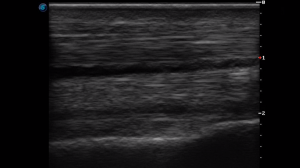

SIMON Ultrasound Database

This ultrasound database is a free resource for students and doctors!

Our collection includes videos of dogs, cats, horses, cows, humans, and many other species!